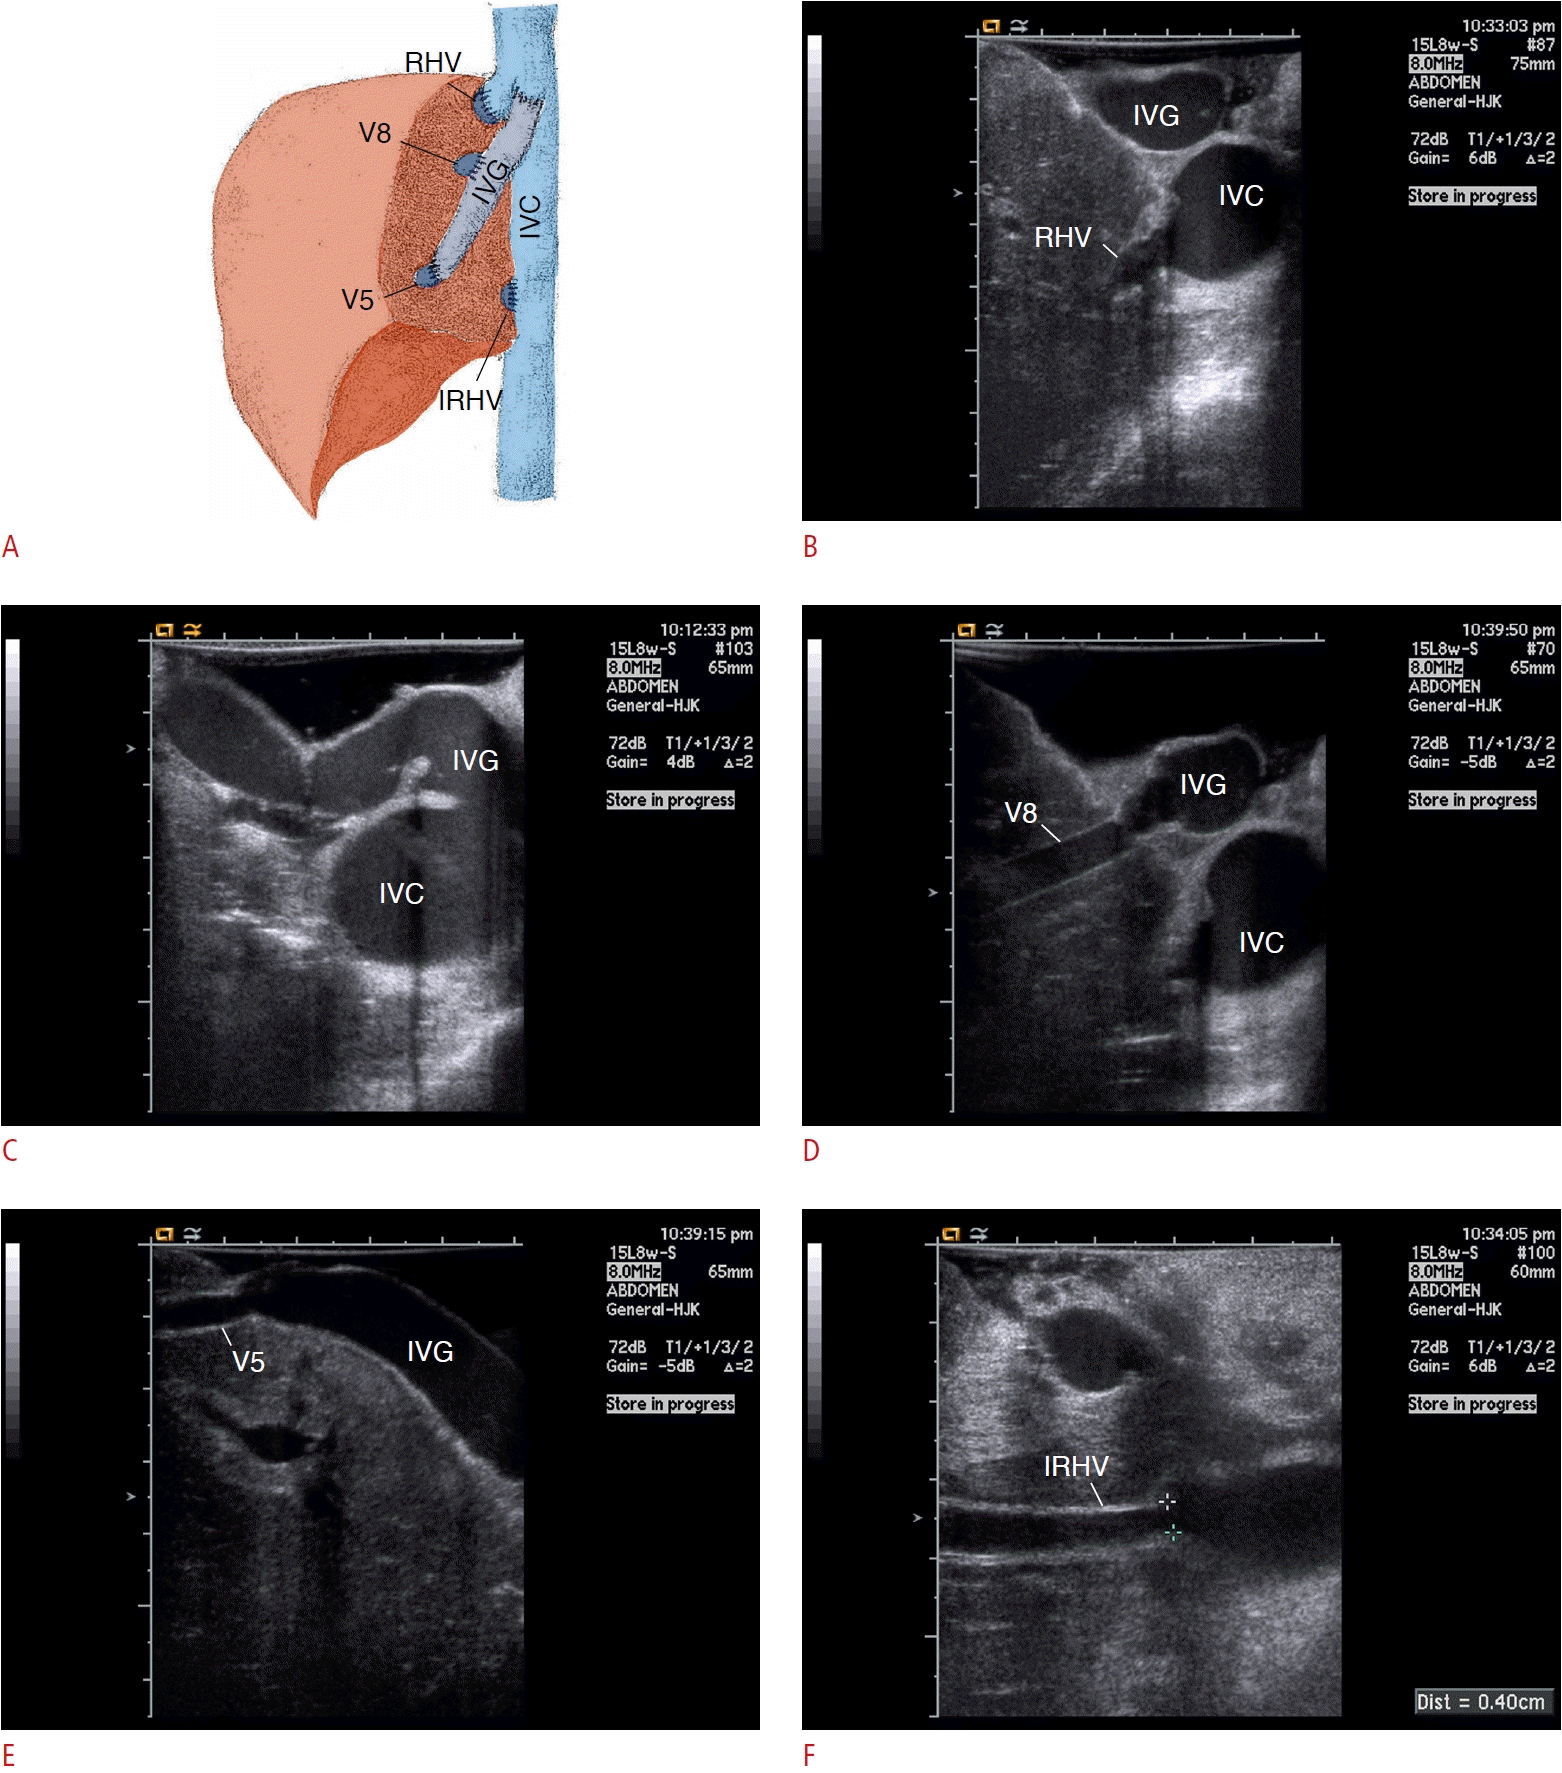

Fig. 7.

Multiple hepatic venous-outflow reconstruction.

A. An illustration shows multiple hepatic venous-outflow reconstruction, a most characteristic feature of living donor liver transplantation with modified right-lobe graft. B-F. All of these hepatic veins are clearly demonstrated by intraoperative sonography with high-frequency transducer. IVC, inferior vena cava; IVG, interposition vein graft; RHV, right hepatic vein; IRHV, inferior right hepatic vein; V8, middle hepatic vein tributary in segment 8; V5, middle hepatic vein tributary in segment 5.

A hallmark that differentiates LDLT with a right lobe graft from cadaveric whole-liver transplantation is the presence of multiple hepatic venous outflows. Although the right HV (RHV) typically serves as the primary drainage route for the right-lobe graft, a substantial portion of right anterior sector drains into the middle HV (MHV). However, because the MHV is usually preserved in the donor for safety reasons, the right anterior sector is prone to congestion unless the corresponding HV tributaries are reconstructed using an interposed venous conduit. Similarly, a considerable portion of the right posterior sector may drain into the inferior RHV (IRHV). Therefore, without anastomosis of IRHV to inferior vena cava, the right posterior sector may also become congested. Nonetheless, the indication for reconstruction of these venous tributaries remains subject of debate, as the development of intrahepatic veno-venous collaterals may save these areas from congestion [4].

When the MHV tributaries of the anterior sector are large enough (>5 mm caliber), they are reconstructed via interposition vein graft (autologous [recipient’s great saphenous vein, external iliac vein, umbilical collateral vein], cryopreserved cadaveric cavo-iliac vein, or polytetrafluoroethylene grafts) into the recipient’s MHV and/or left HVs or inferior vena cava) in our institution. Similarly, inferior RHVs are directly anastomosed to the inferior vena cava, if large enough (>5 mm caliber). All of these HVs, together with RHV, are confidently evaluated by IOS (Fig. 7).